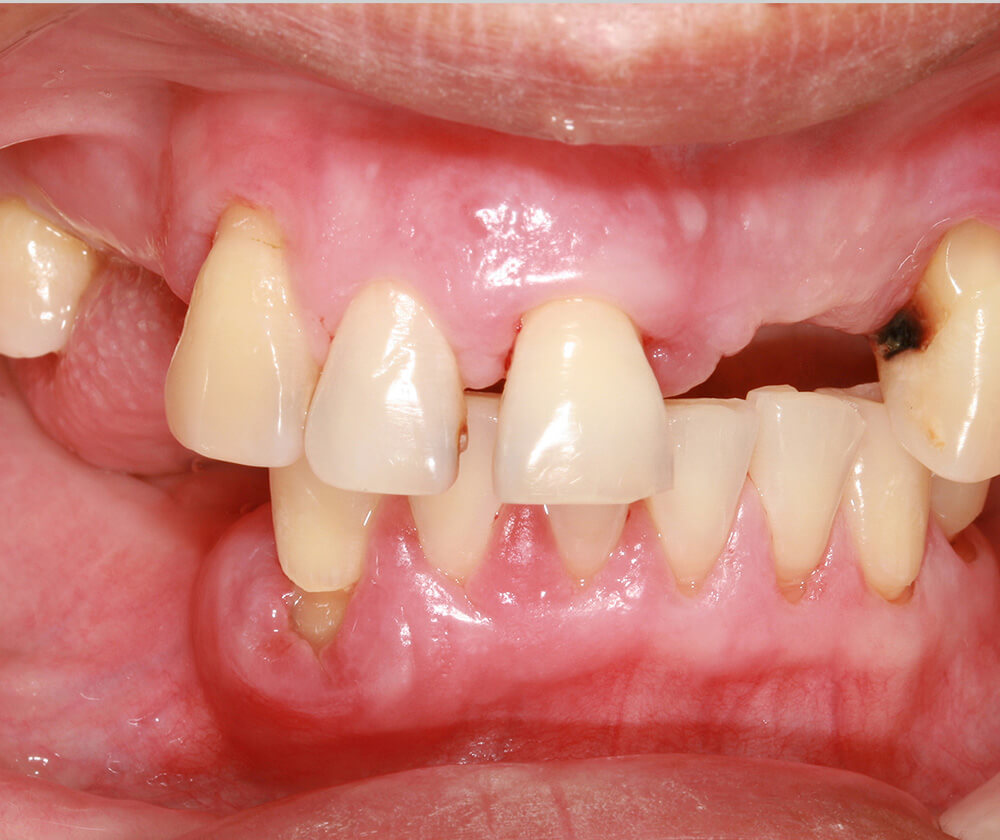

かみ合わせ、見た目にこだわり

歯がボロボロの方の治療も、当院にお任せください。まずはお口の状態を確認し、悪化の原因を丁寧に究明します。入れ歯もインプラントも、見た目や噛み合わせまで考慮して改善を図ります。